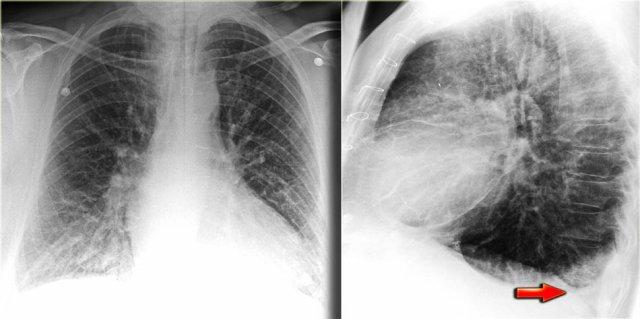

Hình ảnh bên trái là của một bệnh nhân có tràn dịch màng phổi hai bên.

Lưu ý rằng tổn thương này thể hiện rõ hơn trên tư thế chụp nghiêng.

Tràn dịch màng phổi không phải lúc nào cũng biểu hiện dưới dạng hình mức dịch tại góc sườn hoành.

Tràn dịch dưới phổi có thể đi theo đường viền của cơ hoành, khiến việc nhận diện trở nên khó khăn.

Trong những trường hợp này, cách duy nhất để phát hiện tràn dịch màng phổi là khi nhận thấy khoảng cách tăng lên giữa bóng hơi dạ dày và đáy phổi.

Dạ dày thường nằm ngay dưới cơ hoành, do đó, trên phim chụp thẳng (PA) tư thế đứng, bóng hơi dạ dày luôn phải xuất hiện ở vị trí sát với cơ hoành và đáy phổi.

Hình ảnh bên trái là của một bệnh nhân có các dấu hiệu của suy tim sung huyết (CHF).

Thoạt nhìn, bạn có thể có ấn tượng rằng cơ hoành đang ở vị trí cao.

Tuy nhiên, khi nhận thấy khoảng cách tăng lên giữa bóng hơi dạ dày và đáy phổi, bạn sẽ nhận ra rằng có một lượng lớn dịch màng phổi ở cả hai bên (mũi tên).